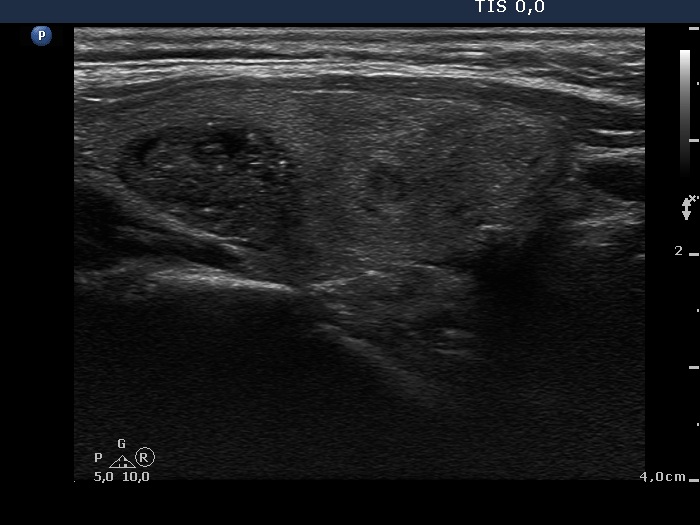

Second examination (second row of images):

Clinical presentation: The patient was referred for a follow-up examination.

Palpation remained unchanged.

Functional state: euthyroidism with TSH 2.11 mIU/L.

Ultrasonography. Both the size and the presentation of the nodules remained unchanged.

We may have doubt about the origin of echogenic figures, if we rely on the analysis of images. However, video proves that most of these granules and lines are related to tiny ventral cystic areas. It means that they are back wall cystic figures caused by posterior enhancement. Moreover, it is worth taking into account that the nodule lacks other suspicious characteristics which would be an unusual finding in the event of such large number of microcalcifications.

This study illustrates the difficulty of interpretation of hyperechogenic granules. In such cases the thorough analysis of the video is of much greater help than that of the images.